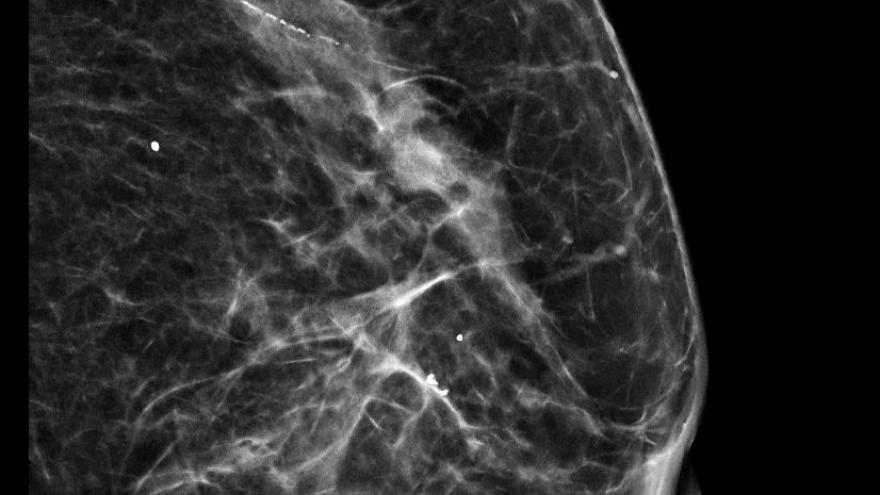

Los equipos de Ginecología y de Radiodiagnóstico del Hospital Santa Cristina trabajan en equipo en la preparación de las pacientes a las que se ha detectado un cáncer de mama antes de intervenir para extraer el tumor, especialmente cuando la lesión es pequeña. Así, con distintos métodos, se localizan las lesiones de forma prequirúrgica para acotar el área a resecar con la cirugía y asegurarse de la extracción completa de la lesión.

Una de las formas más usuales de lograr esa localización pre quirúrgica precisa es el uso de un arpón, un hilo metálico que señala el área de la mama en la que intervenir y que se coloca pocos minutos antes de la entrada en quirófano. Los resultados clínicos y el perfil de seguridad de las semillas son similares a las del arpón y tienen una tasa más baja de complicaciones; son además más cómodas para la paciente y más intuitivas para el cirujano.